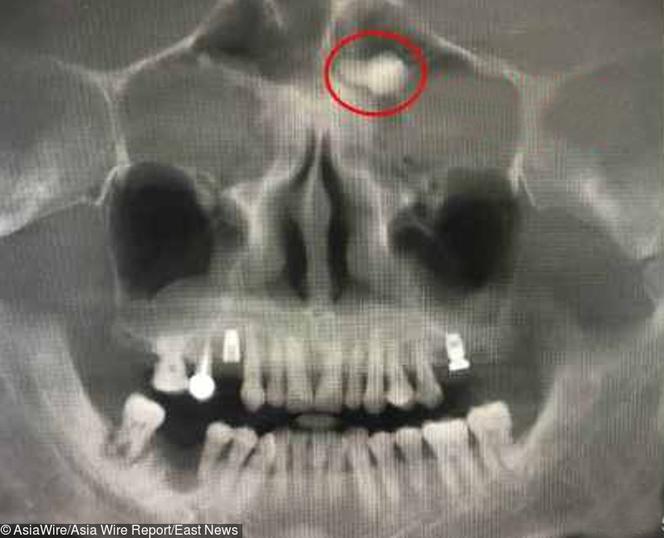

Wyrósł mu ząb nad okiem - Super Express

Wyrósł mu ząb pod okiem